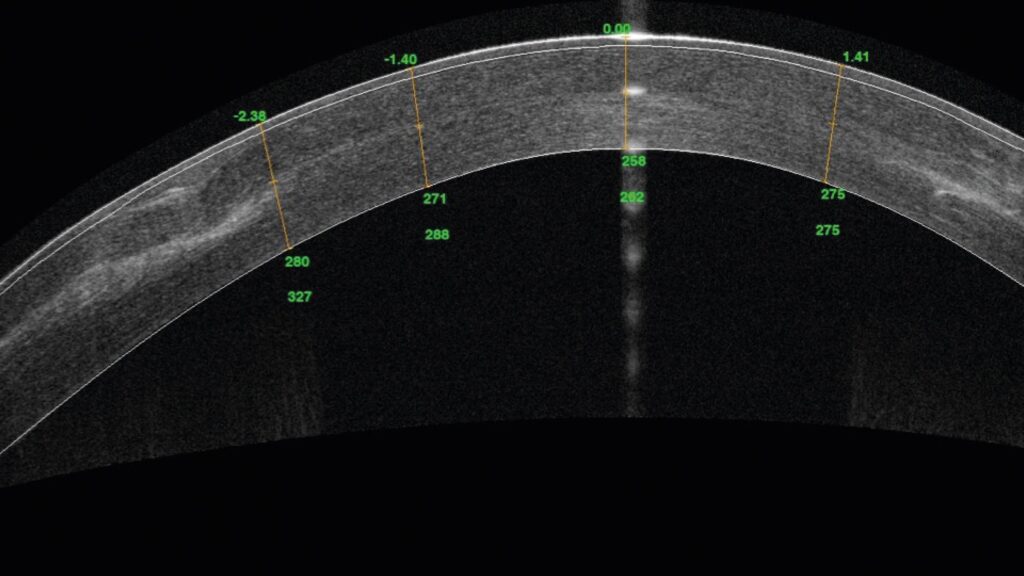

O laser in situ keratomileusis (LASIK) é o método cirúrgico refrativo mais realizado no mundo com excelentes resultados, porém tal método não é isento de riscos. A ectasia pós LASIK é uma complicação grave e se caracteriza por um aumento progressivo da curvatura e afinamento da córnea, resultando em astigmatismo irregular e diminuição da acuidade visual. Sua incidência na literatura atual é de aproximadamente 0,033%. O principal tratamento dessa complicação é o implante de anel intra-estromal com cross-linking. Neste artigo descrevemos um caso de uma mulher de 45 anos submetida a sucessivas tentativas de tratamento de ectasia pós LASIK, com implante de anel intra-estromal bilateral, sem sucesso em um dos olhos. Foi feito o uso do excimer laser topoguiado através do photorefractive keratectomy (PRK) sem o cross-linking, que optamos por não realizar pela estabilidade há anos, pelo risco alto de haze e pela ablação apenas na lamela (que era espessa).A paciente obteve melhorasignificativa da visão e da qualidade de vida. Mantemos o acompanhamento a cada seis meses desde então com a tomografia da córnea.